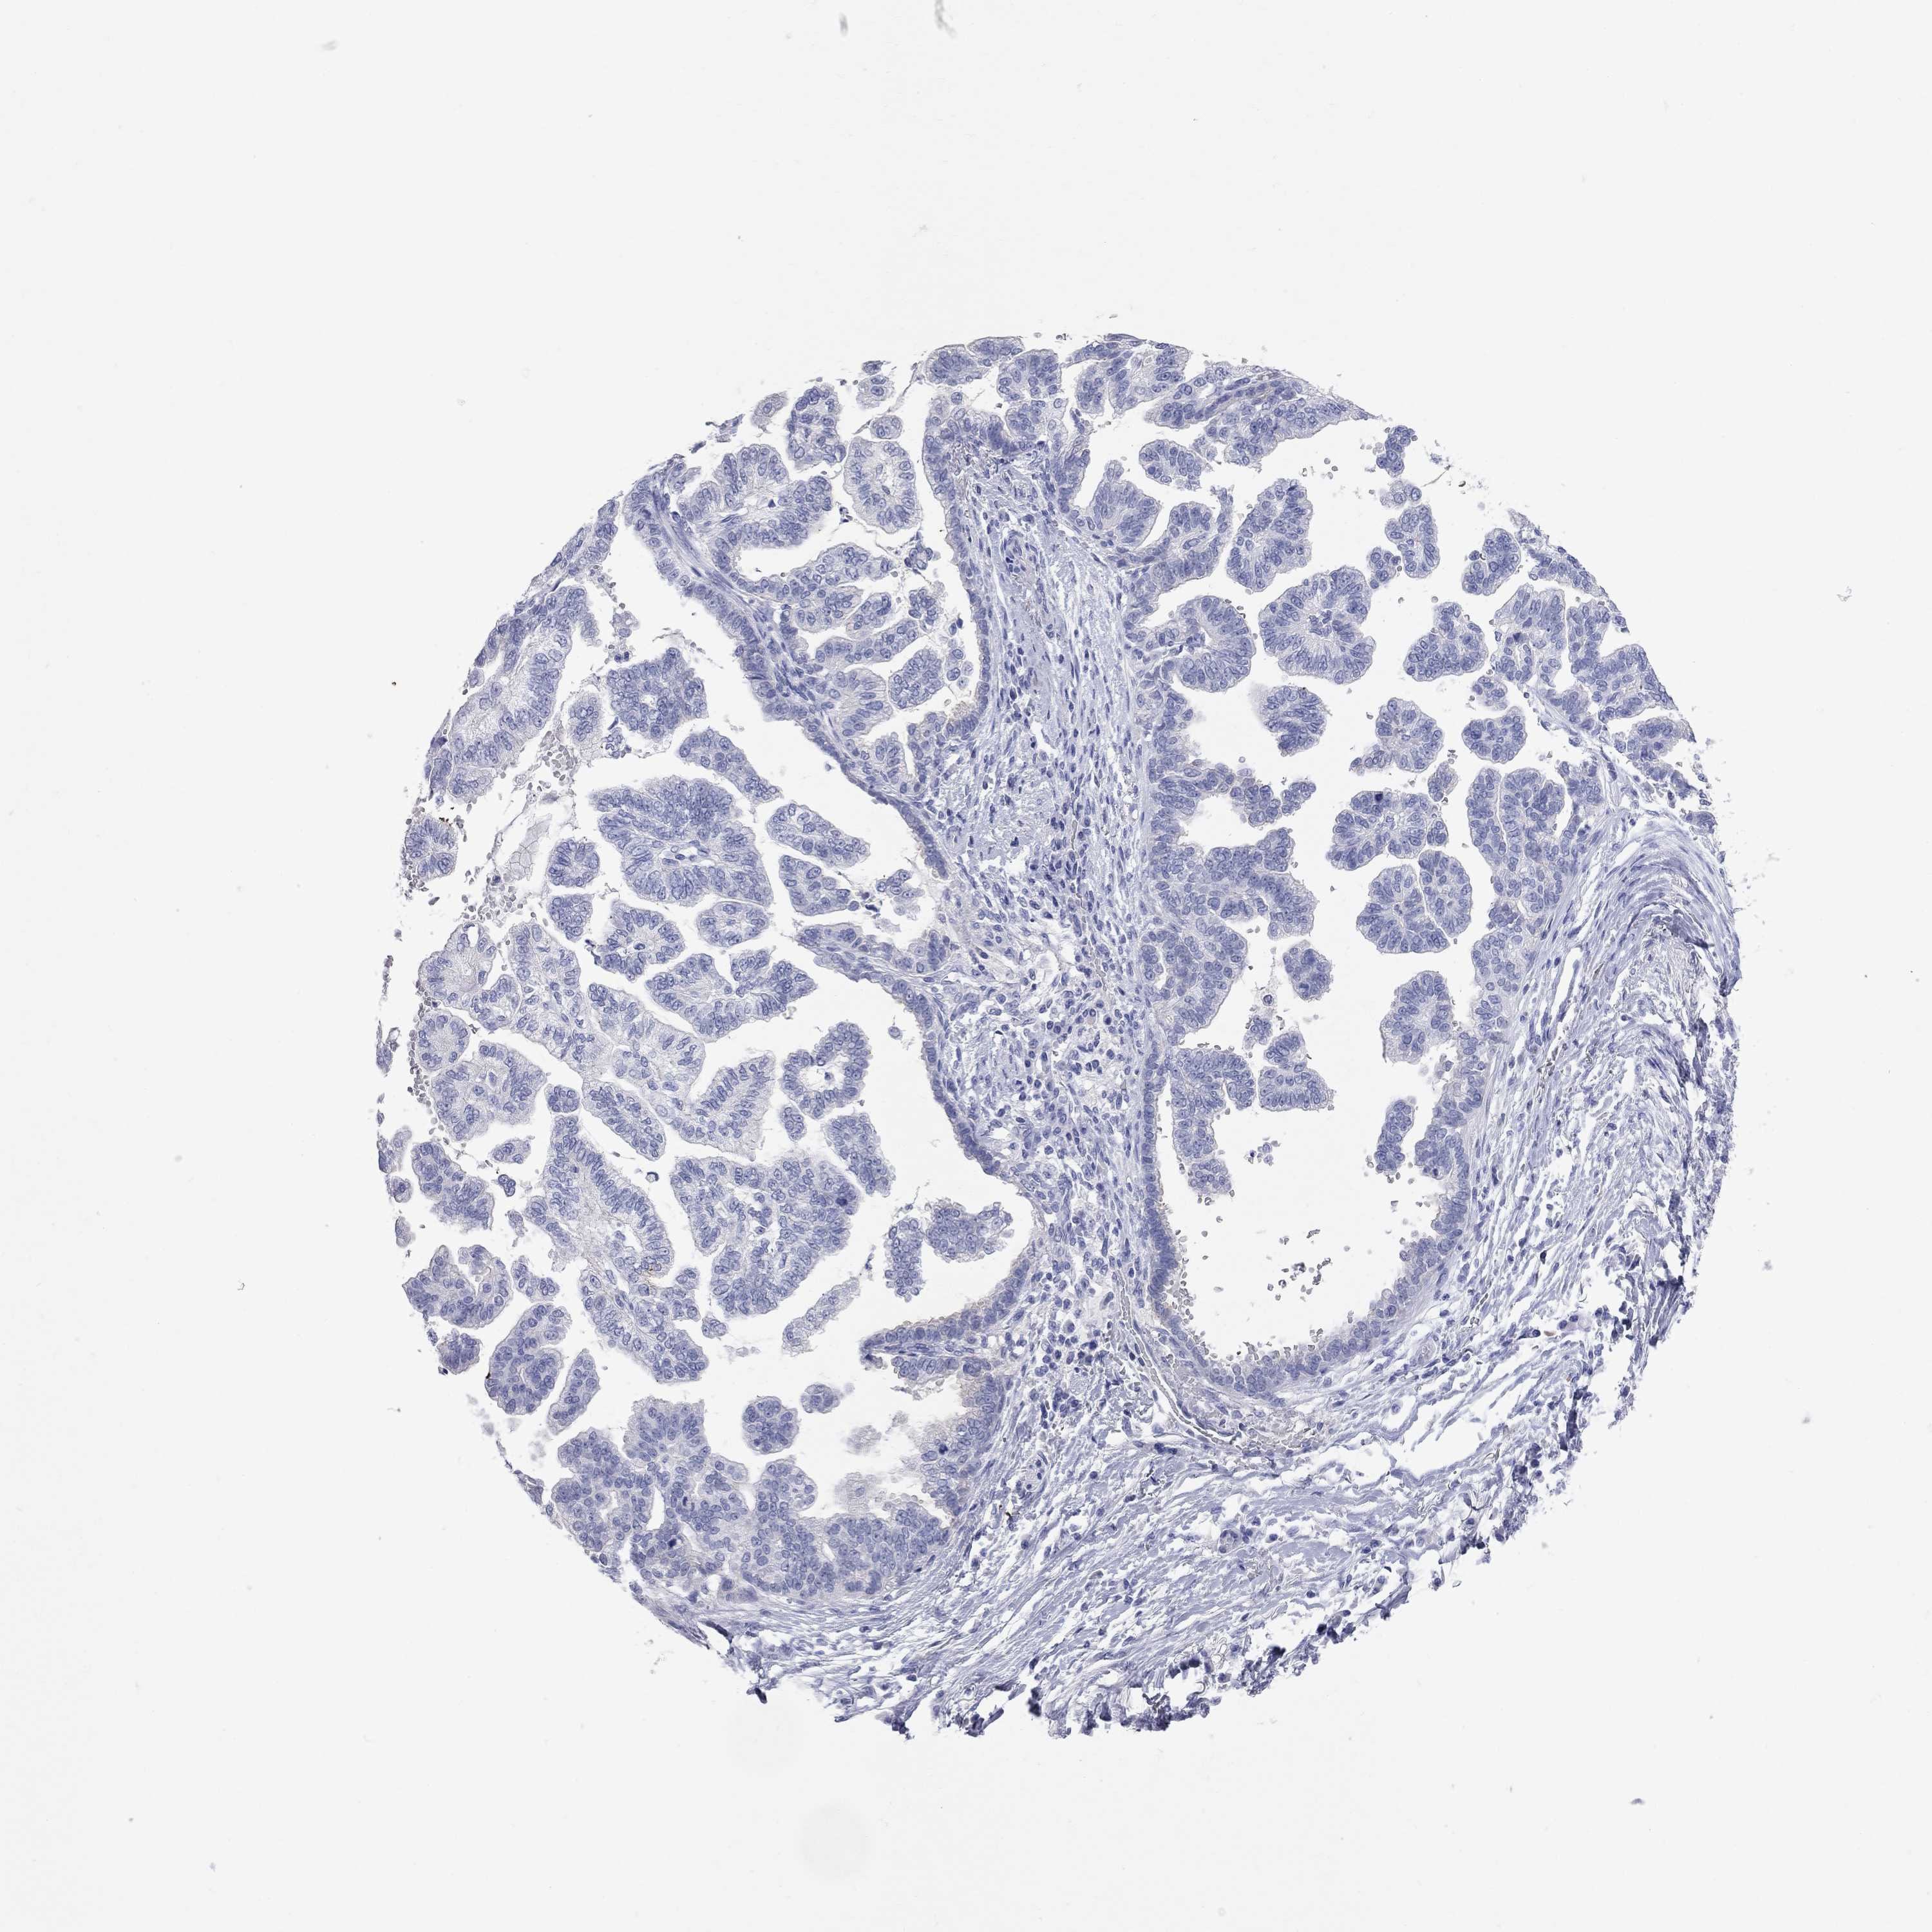

STOMACH CANCER - Protein expressioni

A mouse-over function shows sample information and annotation data. Click on an image to view it in a full screen mode. Samples can be filtered based on level of antibody staining by selecting one or several of the following categories: high, medium, low and not detected. The assay and annotation is described here.

Note that samples used for immunohistochemistry by the Human Protein Atlas do not correspond to samples in the TCGA dataset.

Antibody stainingi

Antibody staining in the annotated cell types in the current human tissue is reported as not detected, low, medium, or high, based on conventional immunohistochemistry profiling in selected tissues. This score is based on the combination of the staining intensity and fraction of stained cells.

Each image is clickable and will lead to virtual microscopy that enables deeper exploration of all samples and also displays staining intensity scores, fraction scores and subcellular localization as well as patient and tissue information for each sample.

Adenocarcinoma, NOS